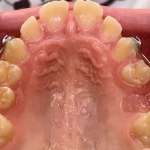

Benefici correlati all’utilizzo del flusso digitale nel trattamento della disgiunzione palatale Premium

La procedura standard per il posizionamento di un disgiuntore rapido palatale prevede una serie di appuntamenti scanditi nel tempo. Scopo di questo lavoro è stato quello di analizzare questi passaggi e sovrapporli a quelli utilizzati per il flusso digitale, valutando pro e contro dei due percorsi.